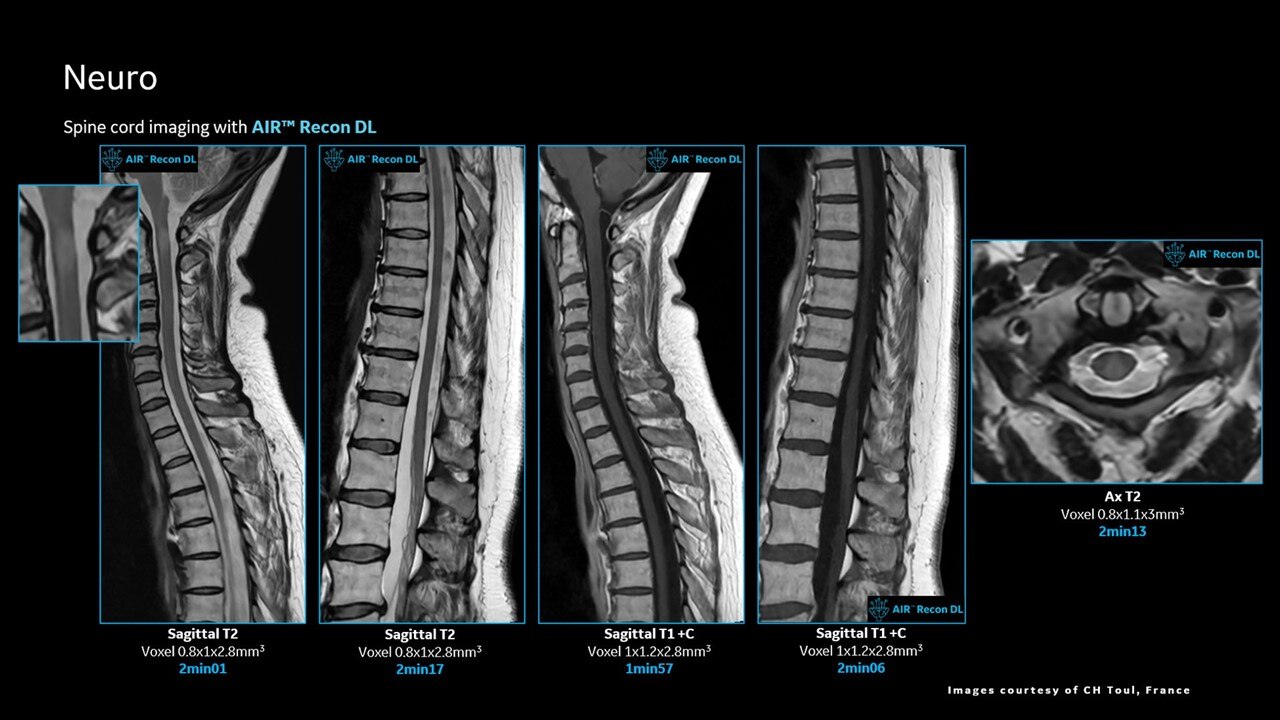

AIR™ Recon DL improves SNR and image sharpness, enabling shorter scan times

Achieve a 25% efficiency gain with Ultra High Efficiency (UHE) gradient system. Fast, clear Total Digital Imaging (TDI) increases SNR by 25%. Improved IQ in 80% of cases without added time. Acquire higher SNR without a time penalty and get images virtually free of artifact with AIR™ Recon DL.***

Attain a 59% productivity gain in exam setup and 37% reduction in table time with AIR Touch™. Five times faster set-up time and four times fewer mouse clicks with AIR x™. Achieve up to a 50% faster acquisition time with AIR™ Recon DL.***